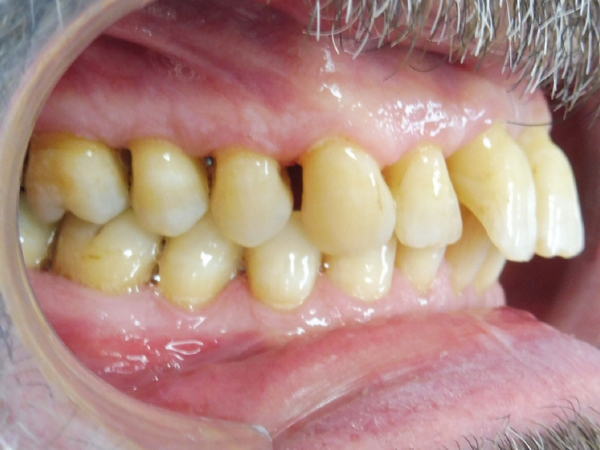

Après traitement orthodontique et réalisation d’une attelle coulée collée (courtoisie Dr Patrick Fournier)